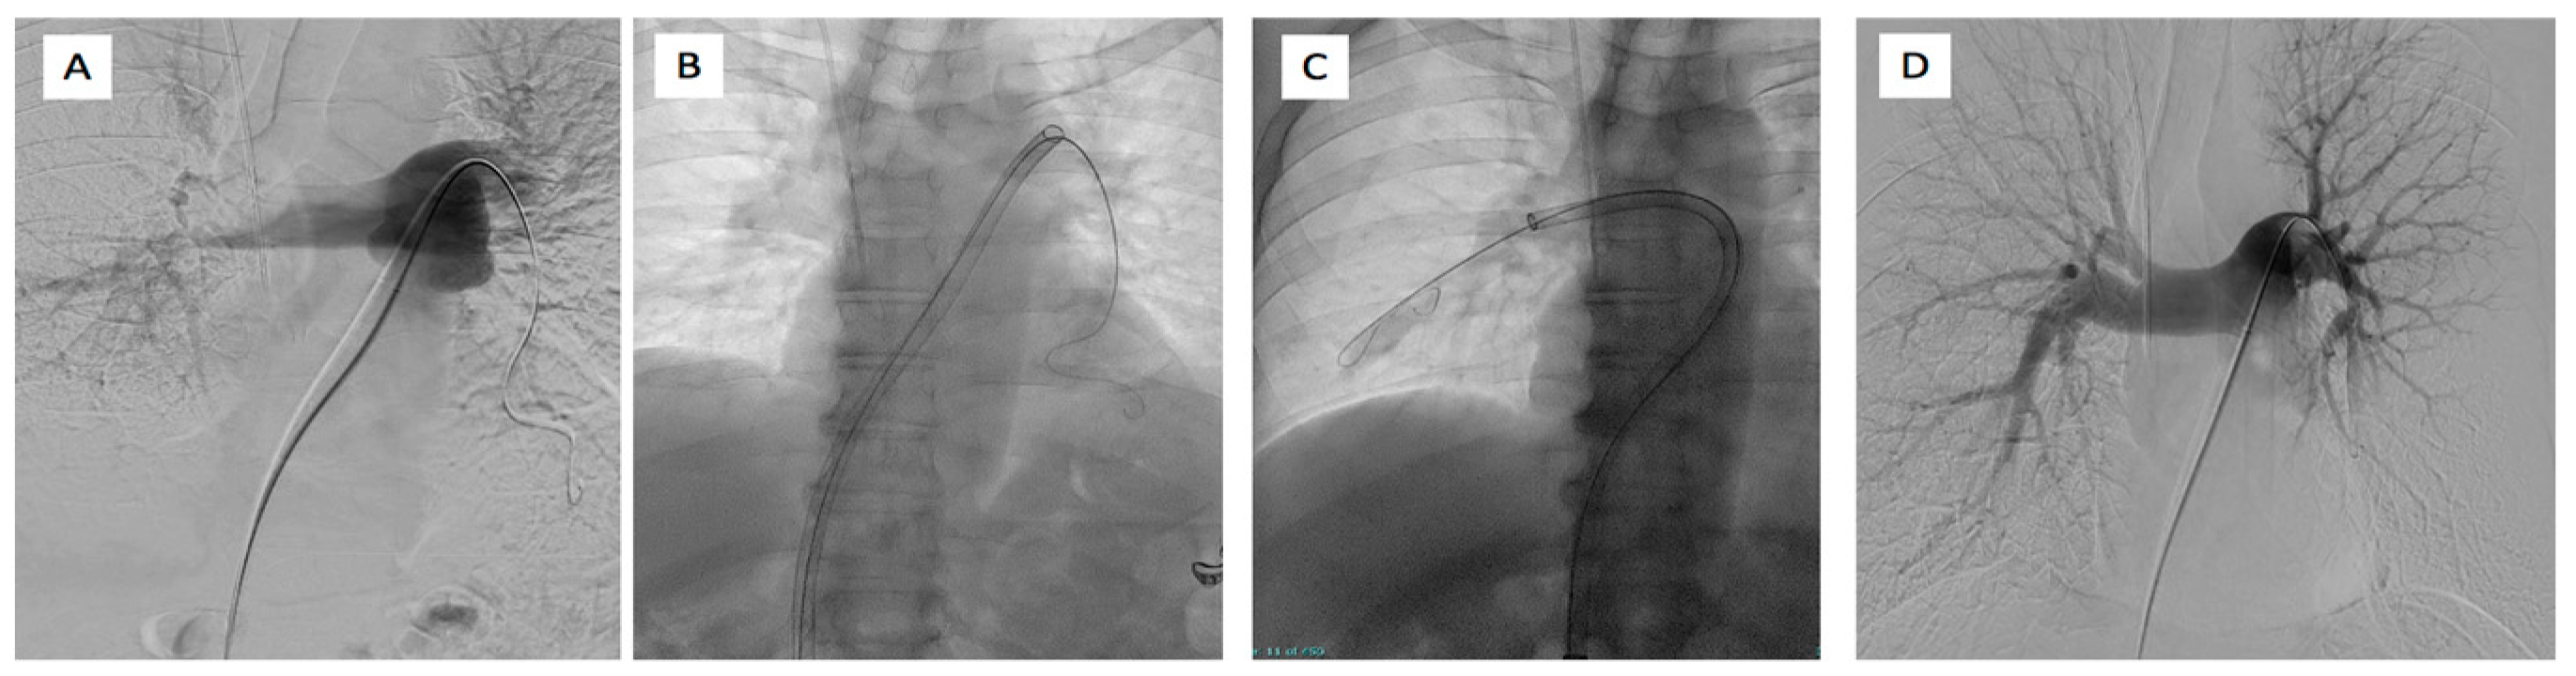

5.2. EkoSonic Endovascular System (EKOS)

5.3. FlowTriever System (Inari Medical)

5.4. Indigo Aspiration System (Penumbra Inc.)

5.5. Other Devices